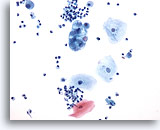

Figure 109

Bronchial wash

A cluster of adenocarcinoma is admixed with respiratory macrophages.

20x